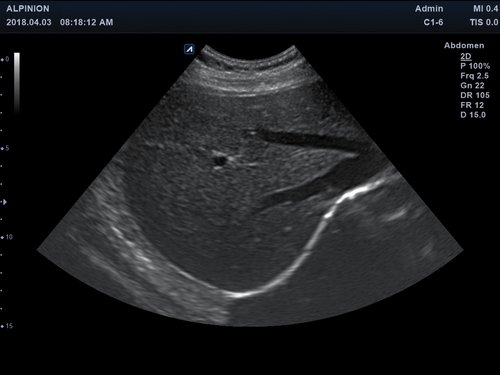

Das Alpinion minisono ist ein tragbares Hand-Ultraschallgerät, das eine sichere und schnelle Diagnostik u. a. in den Anwendungsbereichen Abdomen, MSK, Vaskulär, kleine Organe sowie Bauch und Brust bietet. An das minisono kann über USB-Kabel entweder eine Linear-Sonde oder eine Konvex-Sonde angeschlossen werden. Die komplette ultraschallspezifische Hardware ist in den Griffstücken integriert.

• Abdomen

Anwendungsbereiche Abdomen MSK, Nerven, Karotis, periphere Gefäße, Schilddrüse, Mamma

Bildgebungs-Modi B-Modus, CF, M, PW, PD B-Modus, CF, M, PW, PD

• B-Modus: Darstellung zweidimensionale Bilder anatomischer Strukturen